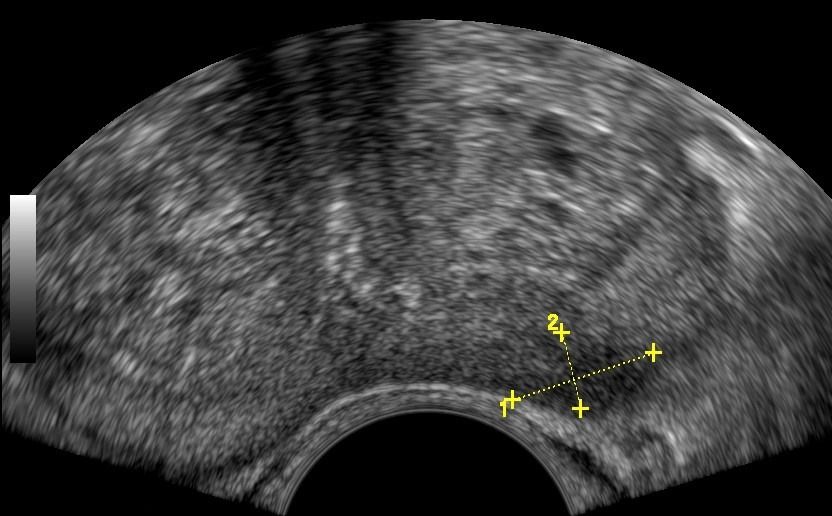

- Prostate: It allows for a detailed assessment of the prostate's morphology and size.

- Peripheral Prostate Zone: The exam can detect focal lesions, such as neoplasms, in the peripheral zone of the prostate.

- Central Prostate Zone: The central zone can be checked for the presence of inflammation, abscesses, calcifications, or other space-occupying lesions.

- Examination: The exam begins with a Lower Abdominal Ultrasound (suprapubic) and continues with the transrectal exam after urination. The transrectal ultrasound is performed using a special probe inserted into the rectum through the anal sphincter. This method provides a comprehensive evaluation of the prostate's morphology.